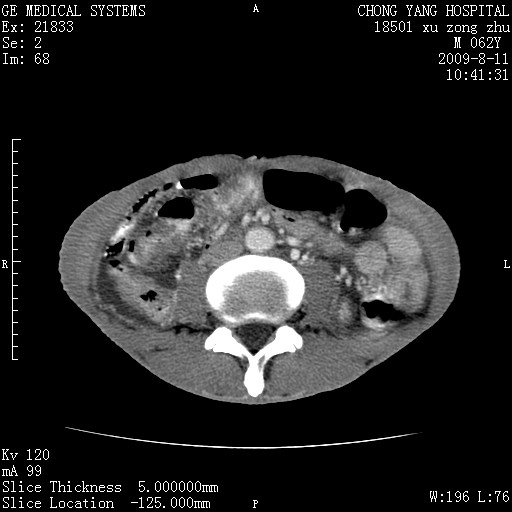

以下是引用杀毒软件在2009-8-11 16:35:00的发言:[br]肝内胆管扩张局限于左叶,胆管内有结石伴肝外胆管结石,胆管壁增厚呈弥漫性并发腹腔积液,胰腺边界模糊。[br][br]考虑---胆总管及肝内胆管结石继发胆管炎及胰腺炎,左肾下极囊肿,腹水。

以下是引用zjzjr在2009-8-11 17:35:00的发言:[br]肝内胆管扩张局限于左叶,胆管内有结石伴肝外胆管结石,胆管壁增厚呈弥漫性并发腹腔积液。[br][br]考虑---胆总管及肝内胆管结石继发胆管炎,左肾下极囊肿,腹水。